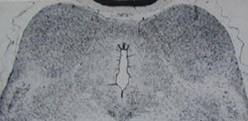

normal